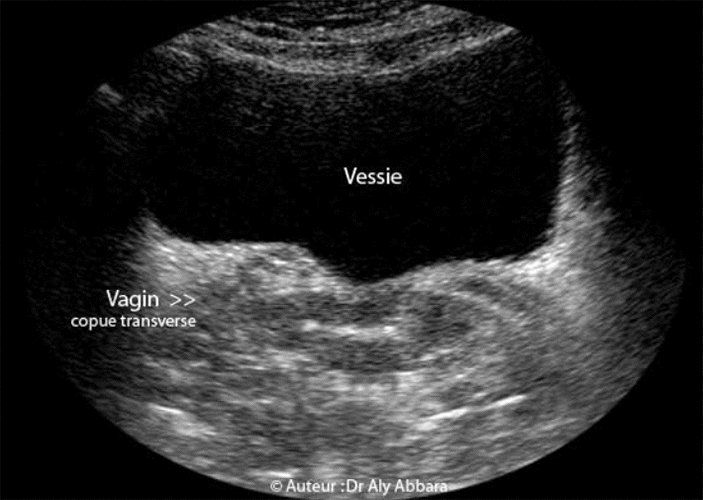

Vagin de femme adulte - Coupe transverse - Echographie et IRM

Coupes échographiques et d'IRM, transversales du pelvis passant par le vagin).

Ces images montrent que le vagin n'est pas un tube ni un canal ni une cavité ouverte en permanence, car ses deux parois, antérieure et postérieure sont appliquées l'une contre l'autre, lui donnant un aspect aplati (contrairement au rectum). Ces parois vaginales s'écartent lors de la pénétration ou l'introduction d'un instrument (spéculum par exemple).

Le vagin est situé dans la cavité pelvienne, entre la vessie et l'urètre en avant et le rectum en arrière ; il se fixe en haut sur le col utérin (عنق الرحم) qui fait saillie dans sa cavité mais les parois vaginales restent séparées du col utérin par un cul-de-sac (رتج) annulaire (ou fornix vaginal) divisé en quatre segments (deux culs-de-sacs latéraux, droit et gauche; un cul-de-sac antérieur et un cul-de-sac postérieur).

• Le vagin n'est pas un tube ni un canal ni une cavité ouverte en permanence, car ses deux parois, antérieure et postérieure sont appliquées l'une contre l'autre, lui donnant un aspect aplati, mais ces parois peuvent s'écarter pour permettre l'introduction du sexe de l'homme, un tampon, un doigt, un instrument médical (spéculum, écarteur vaginal...) ou lors du passage du fœtus au cours de l'accouchement. Donc le vagin est un organe extensible, capable d'épouser la forme de l'organe ou l'objet qu'il contient.